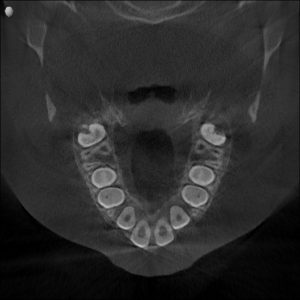

Dental & Jaw Findings

- Narrow upper jaw

- Crowding of upper front teeth

- Deep, high-arched palate

- Early crossbite

- Tongue resting low in the mouth

2. Gentle Maxillary Expansion

A child-friendly expander was used to widen the upper jaw.

This helped to:

- Improve nasal airflow

- Create space for the tongue

- Reduce snoring

- Allow proper jaw growth

- Make room for teeth naturally

After 3 Months

- Increase in jaw width

- Crossbite corrected

- Improved tongue posture